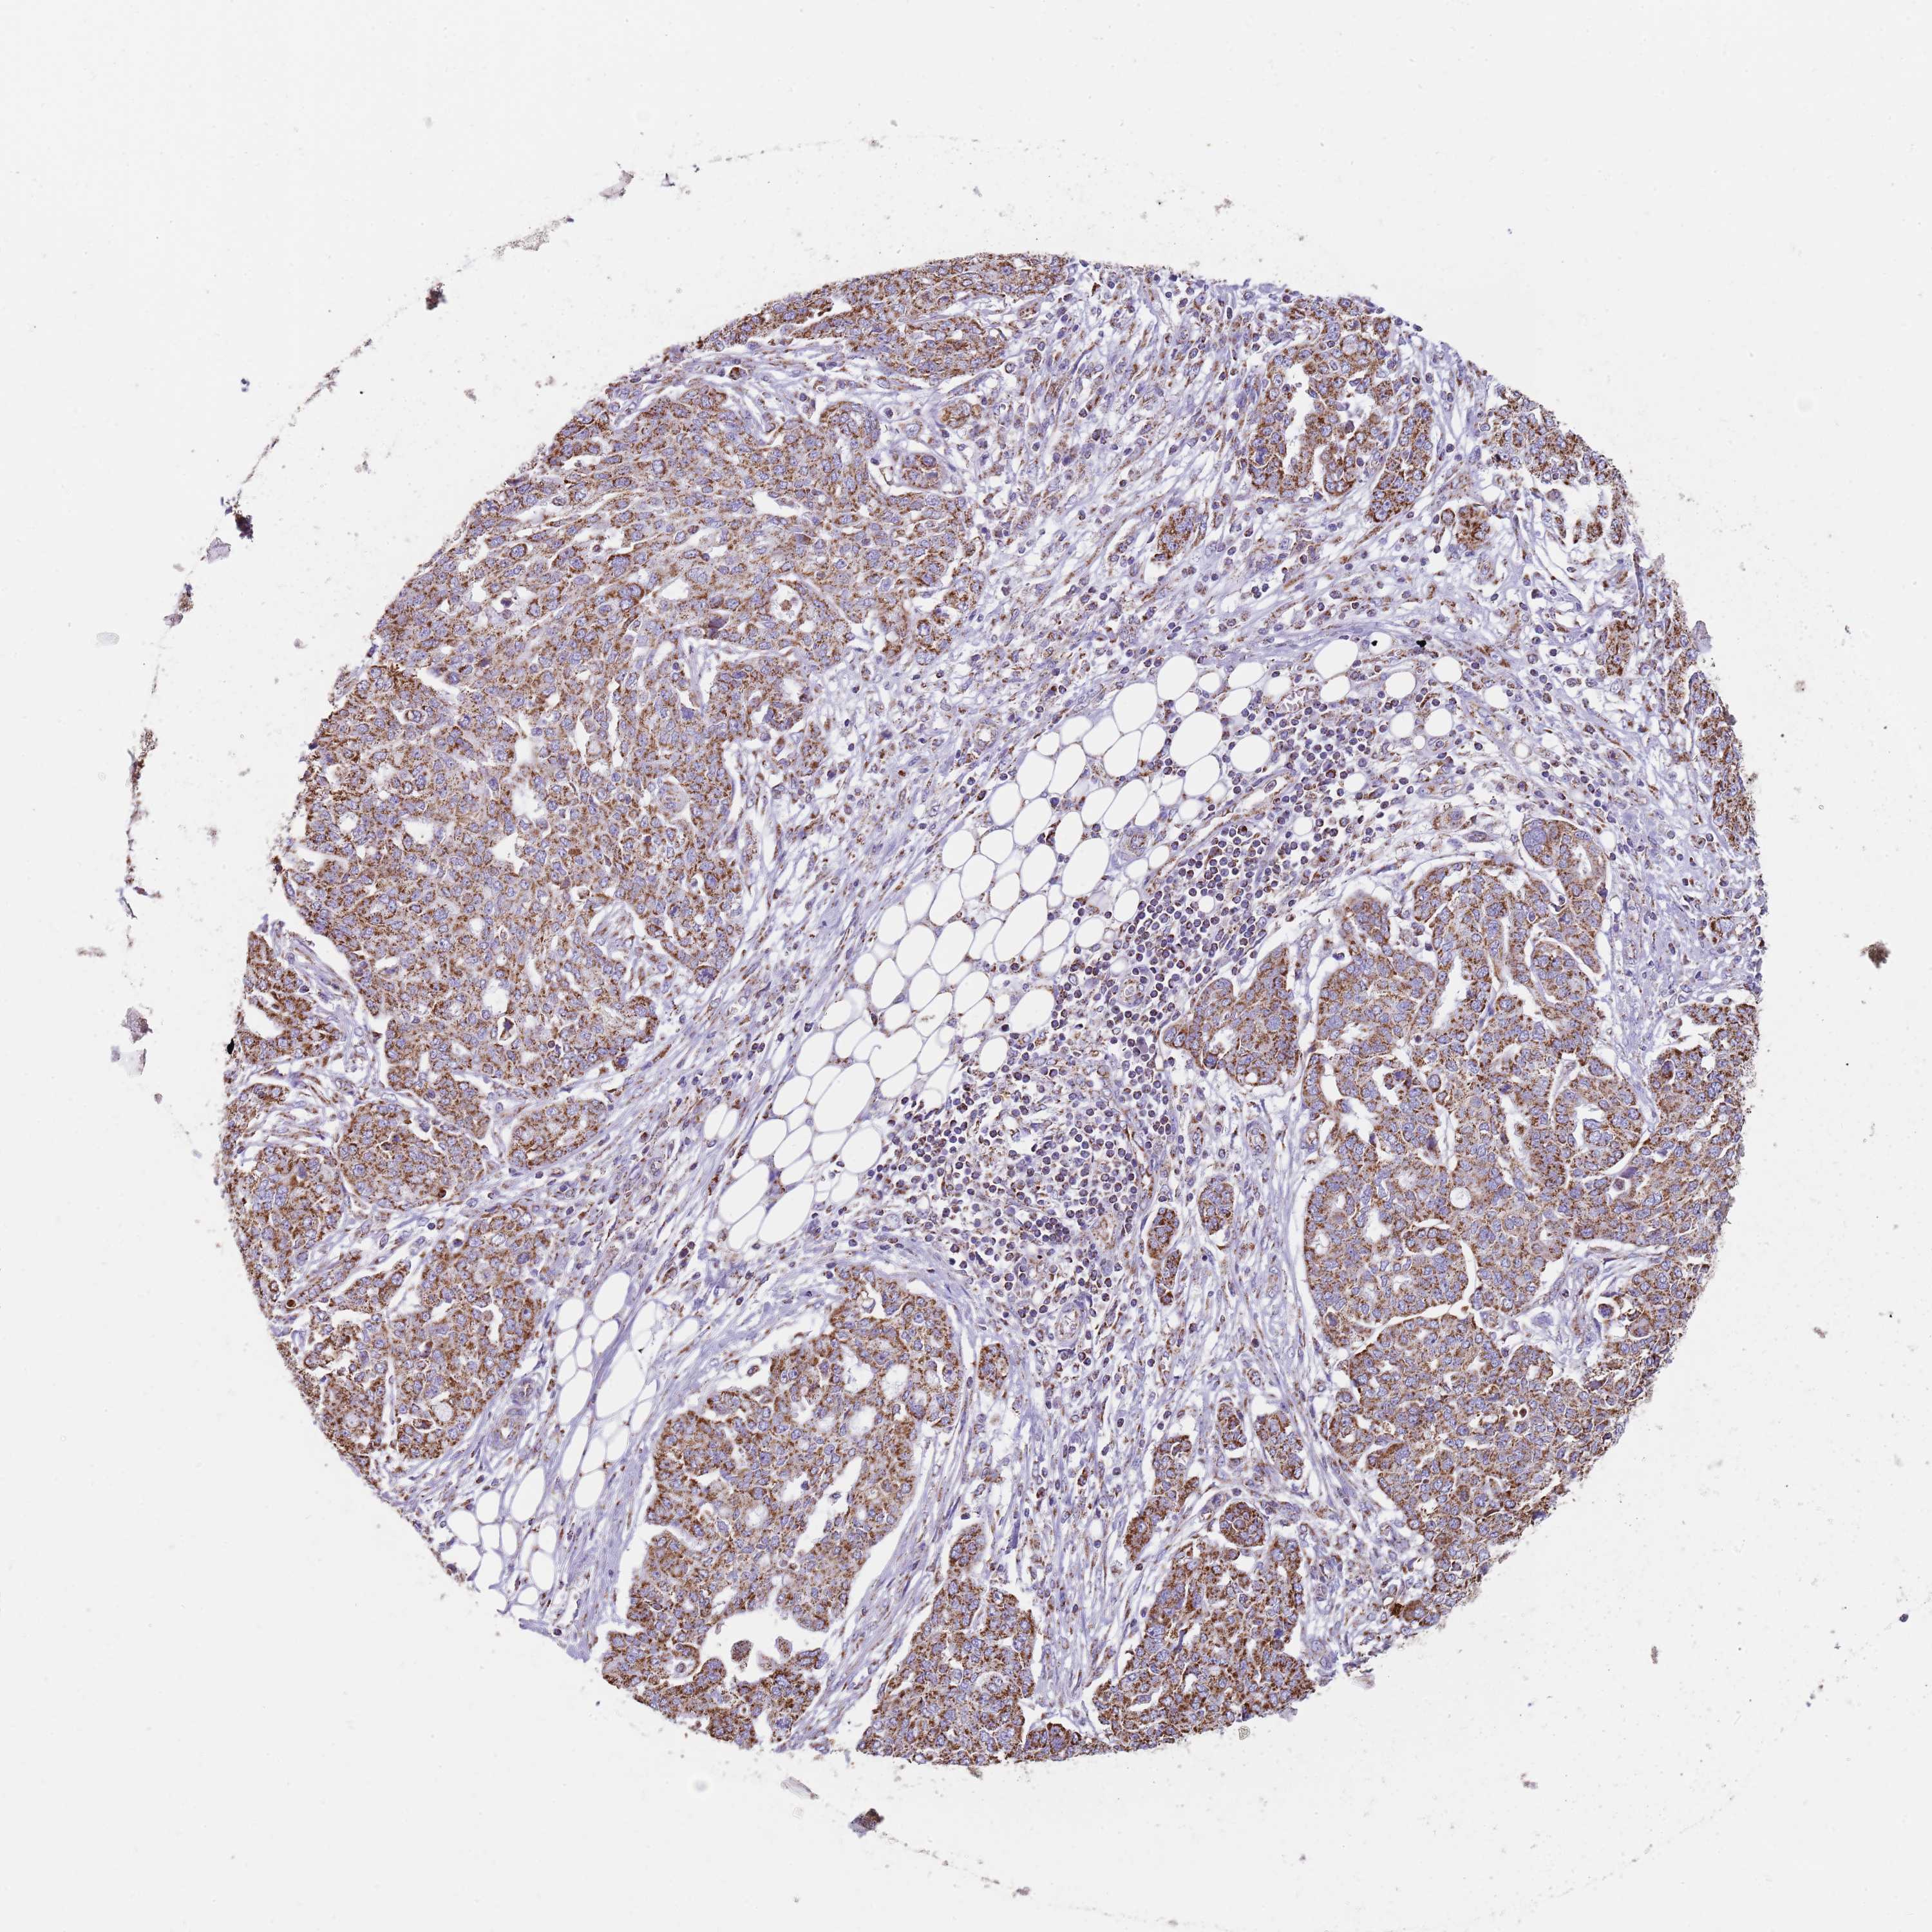

OVARIAN CANCER - Protein expressioni

A mouse-over function shows sample information and annotation data. Click on an image to view it in a full screen mode. Samples can be filtered based on level of antibody staining by selecting one or several of the following categories: high, medium, low and not detected. The assay and annotation is described here.

Note that samples used for immunohistochemistry by the Human Protein Atlas do not correspond to samples in the TCGA dataset.

Antibody stainingi

Antibody staining in the annotated cell types in the current human tissue is reported as not detected, low, medium, or high, based on conventional immunohistochemistry profiling in selected tissues. This score is based on the combination of the staining intensity and fraction of stained cells.

Each image is clickable and will lead to virtual microscopy that enables deeper exploration of all samples and also displays staining intensity scores, fraction scores and subcellular localization as well as patient and tissue information for each sample.

Antibody HPA048392

Staining

High

Medium

Low

Not detected

Intensity

Strong

Moderate

Weak

Negative

Quantity

>75%

75%-25%

<25%

None

Location

Nuclear

Cytoplasmic/membranous

Cytoplasmic/membranous,nuclear

Cystadenocarcinoma, serous, NOS

Carcinoma, NOS